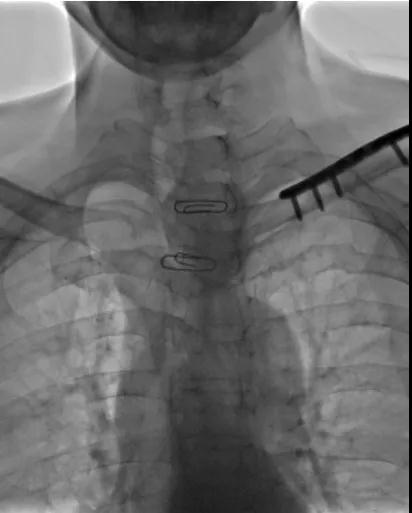

介入术前 成功置入支架

手术当天,在医院胸外科、麻醉科等多方协助下,陈宜新带领科室团队为该患者实施了全麻DSA引导下气道支架置入术,手术全程顺利仅耗时一小时。术后患者呼吸恢复正常,将继续在医院胸外科接受治疗。

△陈宜新为科室年轻医生讲解手术影像